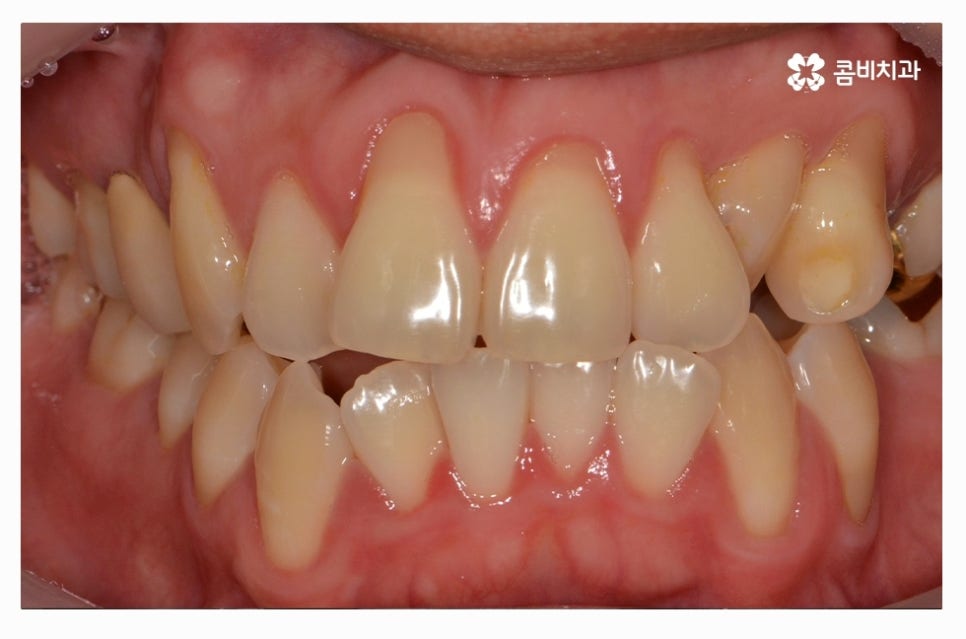

오늘 소개드릴 환자분은 윗니와 아랫니가 제대로 맞물리지 않는

부정교합 사례이며 클리피씨교정을 통해서 치료가 진행된 사례라고 할 수 있어요.

부정교합은 심미적인 부분 외에도 기능적인 부분에 있어서

불편함을 느낄 수밖에 없고 청결관리가 어려워서 나이가 들수록

각종 구강질환이 발생할 확률이 높아질 수 있어요.